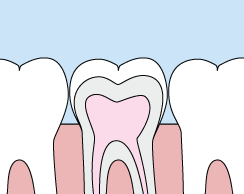

Crowns are a cosmetic restoration used to improve your tooth’s shape or to strengthen a tooth. Crowns are most often used for teeth that are broken, worn, or have portions destroyed by tooth decay.

A crown is a "cap" cemented onto an existing tooth that usually covers the portion of your tooth above the gum line. In effect, the crown becomes your tooth’s new outer surface. Crowns can be made of porcelain, metal, or both. Porcelain crowns are most often preferred because they mimic the translucency of natural teeth and are very strong.

Crowns or onlays (partial crowns) are needed when there is insufficient tooth strength remaining to hold a filling. Unlike fillings, which apply the restorative material directly into your mouth, a crown is fabricated away from your mouth. Your crown is created in a lab from your unique tooth impression, which allows a dental laboratory technician to examine all aspects of your bite and jaw movements. Your crown is then sculpted just for you so that your bite and jaw movements function normally once the crown is placed.